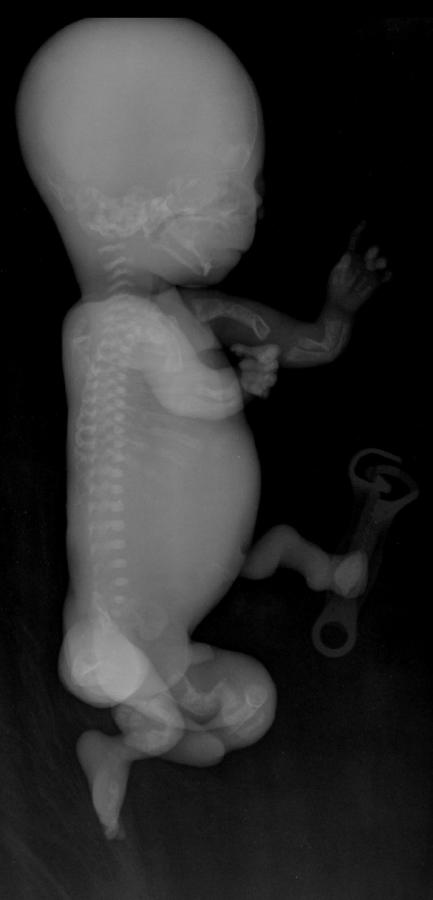

Tipo 2: forma congenita o letale perinatale. I neonati presentano ossa corte e incurvate per le numerose fratture che si sono accumulate in epoca prenatale. Sono presenti sclere blu e dentinogenesi imperfetta. Causa di morte è l'insufficienza respiratoria;

Quella che interessa dal punto di vista della diagnosi ecografica prenatale è l'Osteogenesi Imperfetta tipo II (OMIM 166210) caratterizzata da fragilità ossea con fratture multiple, micromelia severa dovuta alle fratture delle ossa lunghe, ipoplasia toracica severa a volte con fratture costali, ipomineralizzazione diffusa del cranio.  Ecograficamente si manifesta con ossa corte, ricurve e fratturate (le ossa fratturate si presentano angolate); ossa craniche scarsamente ossificate (tanto che la volta cranica può avere una ecogenicità simile a quella della linea mediana) con conseguente migliore evidenza e definizione delle strutture cerebrali e segno caratteristico la deformabilità della teca cranica.;  ipoplasia toracica con fratture costali; IUGR; movimenti fetali scarsi.